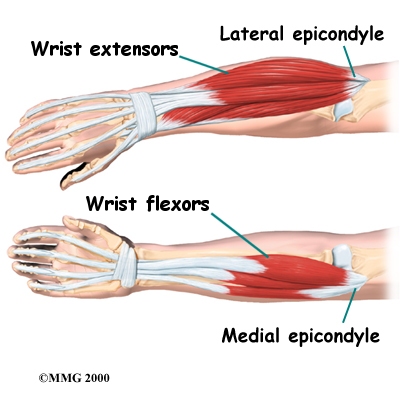

The muscles of the forearm cross the elbow and attach to the humerus. The outside, or lateral boney bump just above the elbow is called the lateral epicondyle. Most of the muscles that straighten the fingers and extend the wrist all come together in one tendon to attach in this area. The inside, or medial, boney bump just above the elbow is called the medial epicondyle. Most of the muscles that bend the fingers and wrist all come together in one tendon to attach in this area. These two tendons are important to understand because they are a common location of tendonitis such as golfer’s elbow (medial common flexor tendonitis) and tennis elbow (lateral common extensor tendonitis.)

Muscles

The main muscles that are important at the elbow have been mentioned above in the discussion about tendons. They are the biceps, the triceps, the wrist extensors (attaching to the lateral epicondyle) and the wrist flexors (attaching to the medial epicondyle).